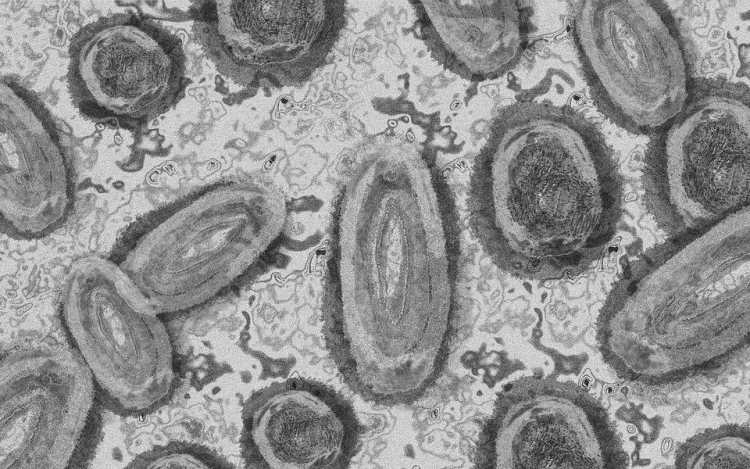

Megfertőződött majomhimlővel egy négyéves kislány Németországban - jelentették kedden német hírportálok az országos közegészségügyi intézet (RKI) adatai alapján.

Németországban első alkalommal mutatták ki a kórokozót gyermek szervezetében.

A kislány két fertőzött felnőttel él együtt a Baden-Württemberg tartományi Pforzheimben. A tartományi egészségügyi minisztérium tájékoztatása szerint elővigyázatosságból vizsgálták meg, miután kimutatták az első fertőzést a háztartásban. Eddig nem jelentkeztek nála a betegség tünetei.

Az RKI-nál május elején regisztrálták az első németországi majomhimlős eseteket. Keddig 2982 igazolt fertőződést jegyeztek fel. A betegség mind a 16 tartományban megjelent.

Az intézet ismeretei szerint a vírus elsősorban szexuális úton terjed Németországban, főleg férfiak körében. A fertőzöttek szinte mind felnőtt férfiak, csupán hét nő és két kiskorú - egy 15 és egy 17 éves kamasz - van közöttük.

Az esetek többségében a fertőzés enyhe lefolyású betegséggel jár. Halálos áldozatot Németországban még nem regisztráltak.

Az Afrika egyes részein évtizedek óta ismert és ritkán előforduló majomhimlő május óta Európában, Észak-Afrikában és más térségekben is terjed. Az Egészségügyi Világszervezet (WHO) júliusban globális egészségügyi vészhelyzetnek nyilvánította a járványt.